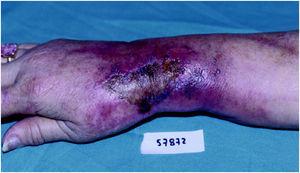

Las lesiones son graves en todos los casos, especialmente en los relacionados con doxorubicina y vinorelbina. Las lesiones se localizaron en la flexura cubital en 4 casos, en la zona distal del antebrazo en tres y en el dorso de la mano en dos. Consistieron en placas eritematosas, edematosas, intensamente dolorosas (fig. 1). Se acompañaron de edema en el área circundante. Las manifestaciones clínicas se iniciaron siempre a las pocas horas de producirse la extravasación. En la mayor parte de los casos el paciente refirió dolor local durante la infusión del agente citostático, lo que permitió evitar extravasación de volúmenes importantes. En 4 casos, las lesiones se complicaron con ulceración después de una semana de evolución (fig. 2).

Fig. 1.--Placa eritematoviolácea mal delimitada cerca de la flexura del brazo.

Fig. 2.--Placa eritematosa con gran área de ulceración y necrosis localizada en la muñeca.